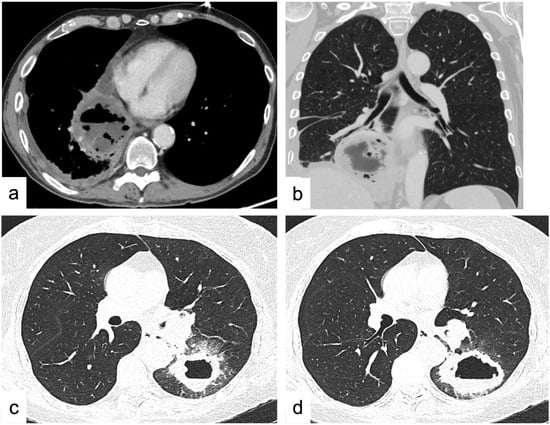

4.1.6. Cavitations and Cysts

- Thalinger, A.R.; Rosenthal, S.N.; Borg, S.; Arseneau, J.C. Cavitation of Pulmonary Metastases as a Response to Chemotherapy. Cancer 1980, 46, 1329–1332. [Google Scholar] [CrossRef] [PubMed]

- Stark, D.; Federle, M.; Goodman, P.; Podrasky, A.; Webb, W. Differentiating Lung Abscess and Empyema: Radiography and Computed Tomography. Am. J. Roentgenol. 1983, 141, 163–167. [Google Scholar] [CrossRef]

- Inchaustegui, C.A.; Wang, K.Y.; Teniola, O.; de Rosen, V.L. Large Septic Pulmonary Embolus Complicating Streptococcus Mutans Pulmonary Valve Endocarditis. J. Radiol. Case Rep. 2018, 12, 18–27. [Google Scholar] [CrossRef]

- Watanabe, T.; Yokoe, M.; Noguchi, Y. Septic Pulmonary Embolism Associated with Periodontal Disease: A Case Report and Literature Review. BMC Infect. Dis. 2019, 19, 74. [Google Scholar] [CrossRef]

- Li, J.; Li, C.; Li, J. Thoracic Manifestation of Wegener’s Granulomatosis: Computed Tomography Findings and Analysis of Misdiagnosis. Exp. Ther. Med. 2018, 16, 413–419. [Google Scholar] [CrossRef] [PubMed]

- Martinez, F.; Chung, J.H.; Digumarthy, S.R.; Kanne, J.P.; Abbott, G.F.; Shepard, J.A.O.; Mark, E.J.; Sharma, A. Common and Uncommon Manifestations of Wegener Granulomatosis at Chest CT: Radiologic-Pathologic Correlation. Radiographics 2012, 32, 51–69. [Google Scholar] [CrossRef]

- Ananthakrishnan, L.; Sharma, N.; Kanne, J.P. Wegener’s Granulomatosis in the Chest: High-Resolution CT Findings. Am. J. Roentgenol. 2009, 192, 676–682. [Google Scholar] [CrossRef]

- Iwasaki, Y.; Nagata, K.; Nakanishi, M.; Natuhara, A.; Harada, H.; Kubota, Y.; Yokomura, I.; Hashimoto, S.; Nakagawa, M. Spiral CT Findings in Septic Pulmonary Emboli. Eur. J. Radiol. 2001, 37, 190–194. [Google Scholar] [CrossRef]